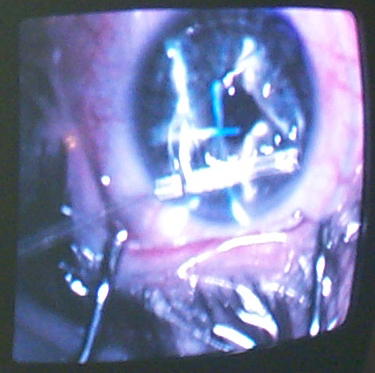

Barcelou Family Gallery Renee Barcelou Dumont 2001 Non - Family Fun Stuff 2001 Scotts Lasik Pics Dcp_4818.jpg

Scotts Lasik Pics

Dcp_4818.jpg